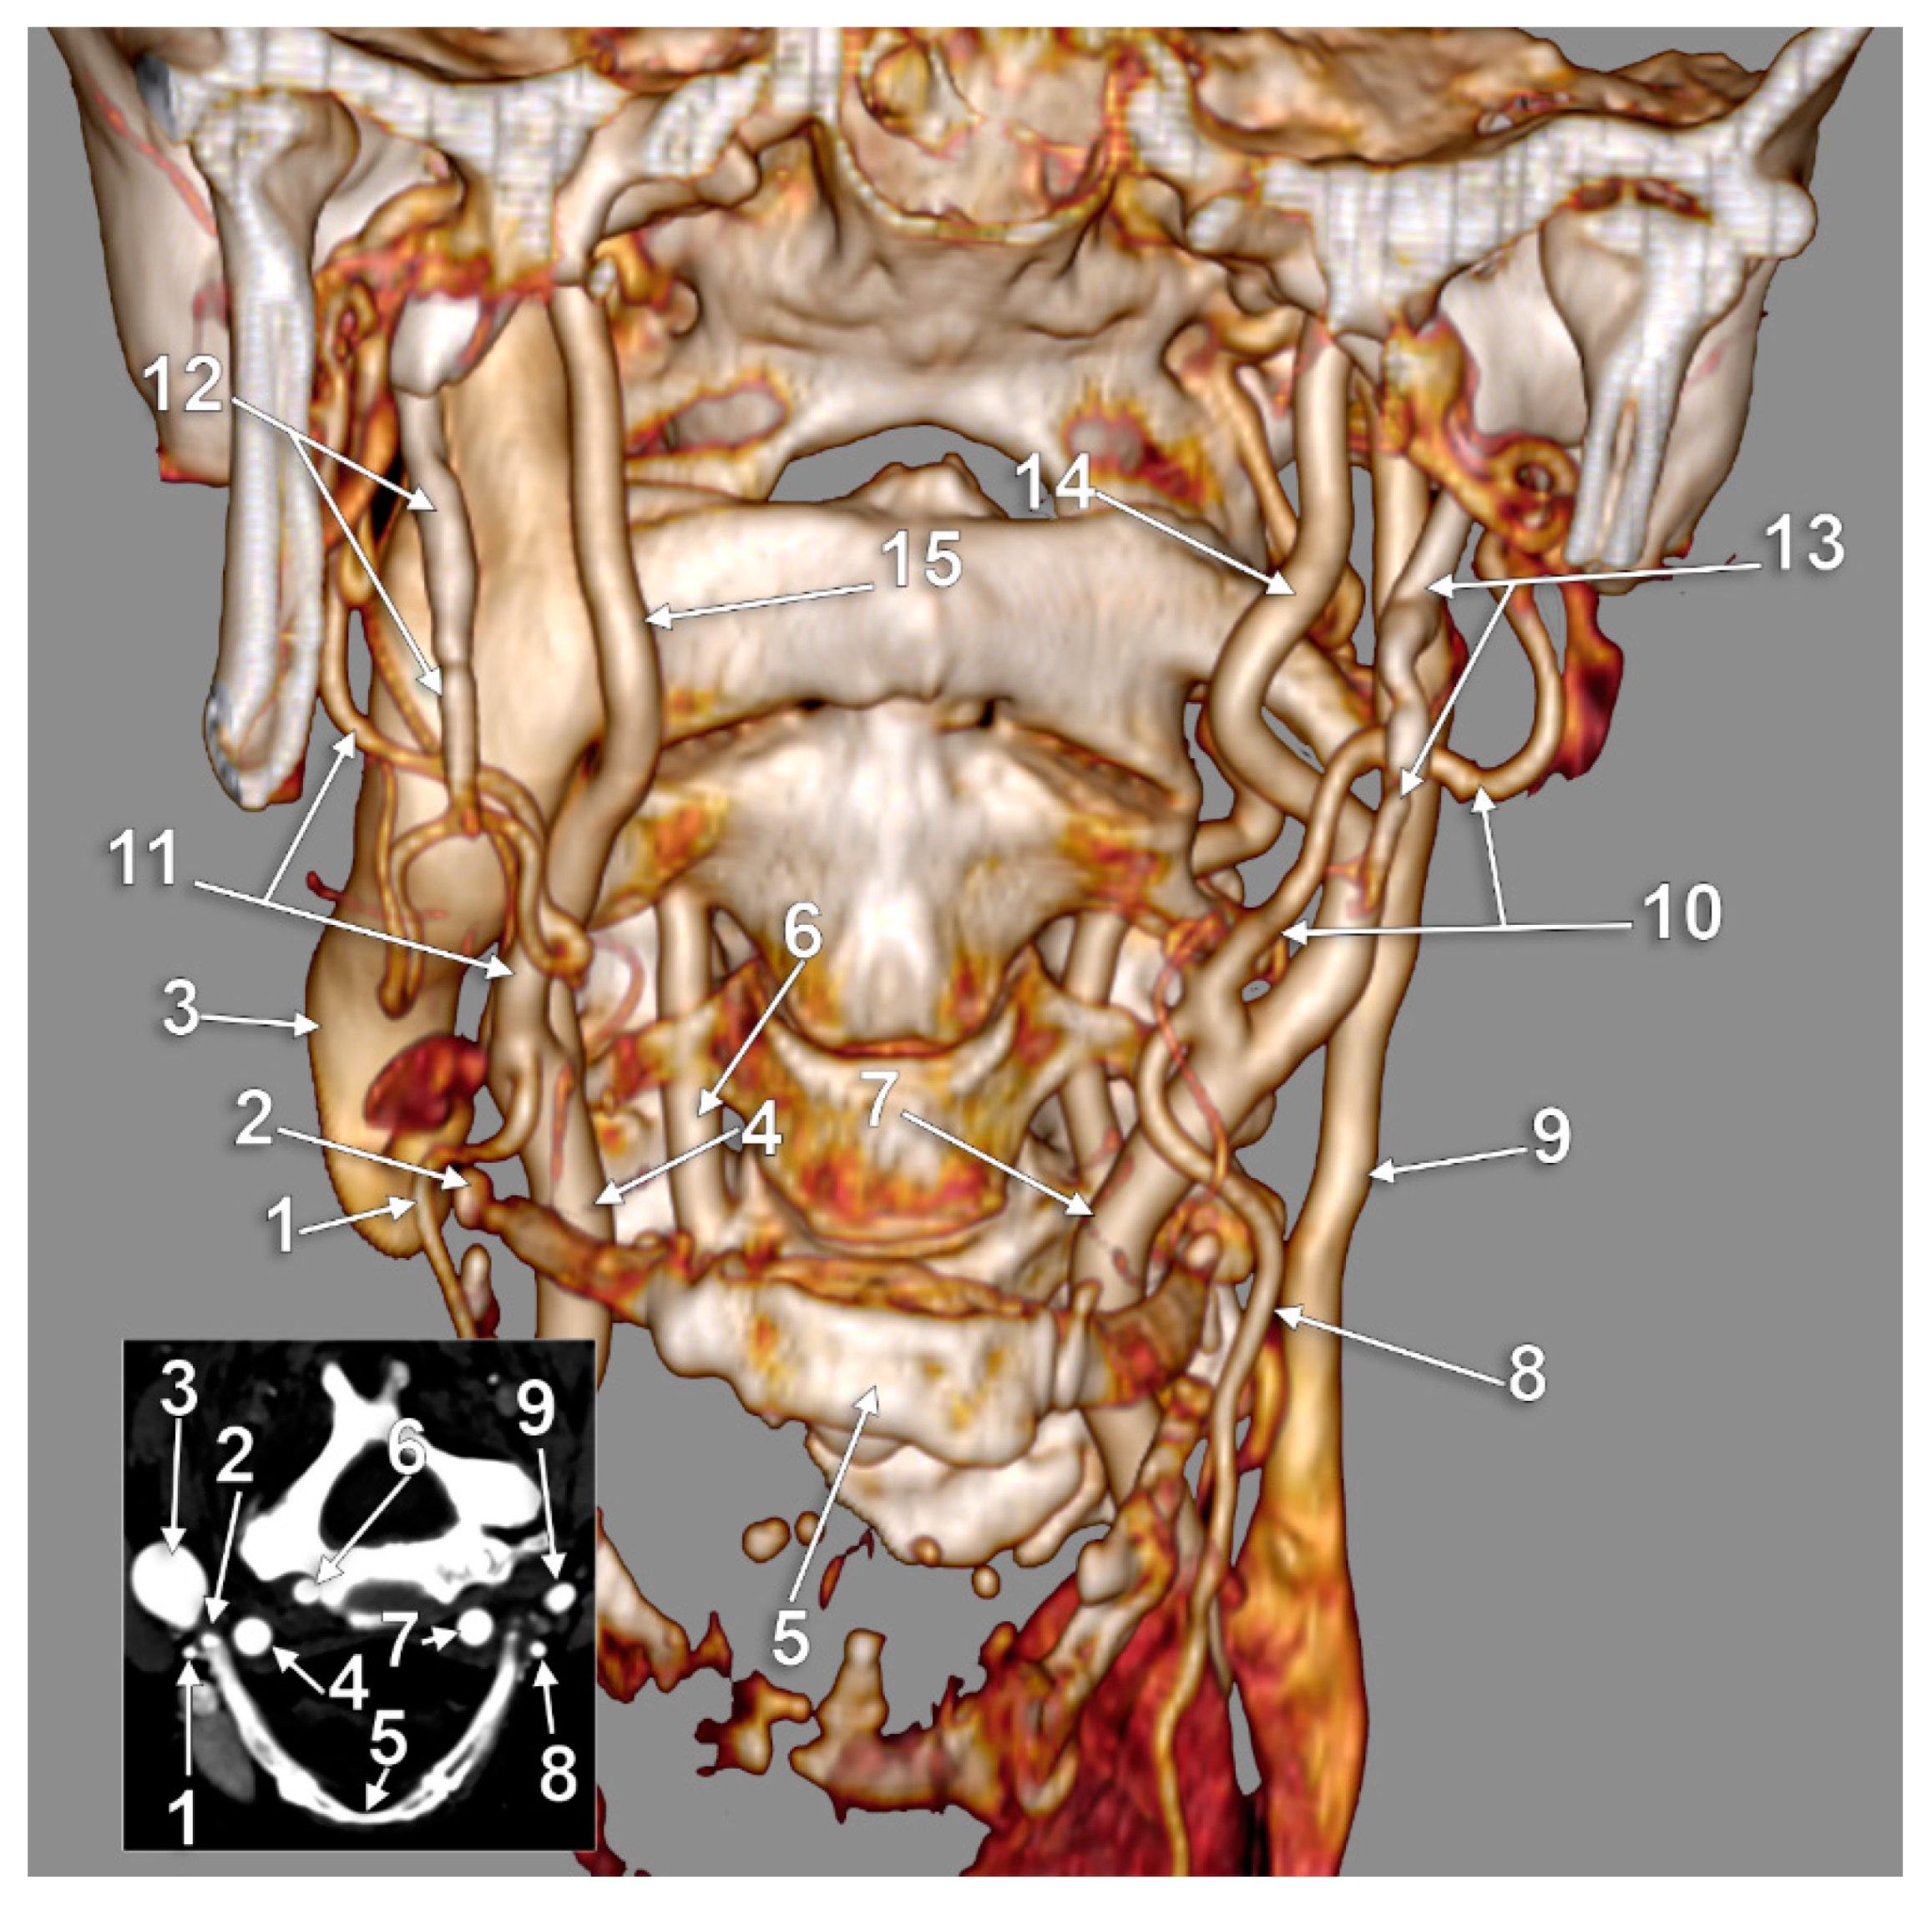

The Carotid–Hyoid Topography Is Variable

3. Results